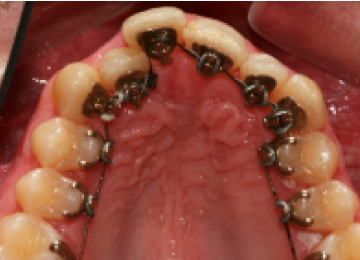

Брекеты: фото До и После

Брекеты могут размещаться как с наружной стороны зубного ряда, так и с обратной (лингвальные), по направлению к ротовой полости. Лингвальная конструкция брекетов может повлиять на произношение и усложнить процесс принятия пищи, но такой вариант установки выбирают за ее незаметность. Тонкая полоска металлического каркаса не привлекает к себе внимания. А если на слизистой щек были травмы, этот вариант становится наиболее предпочтительным.